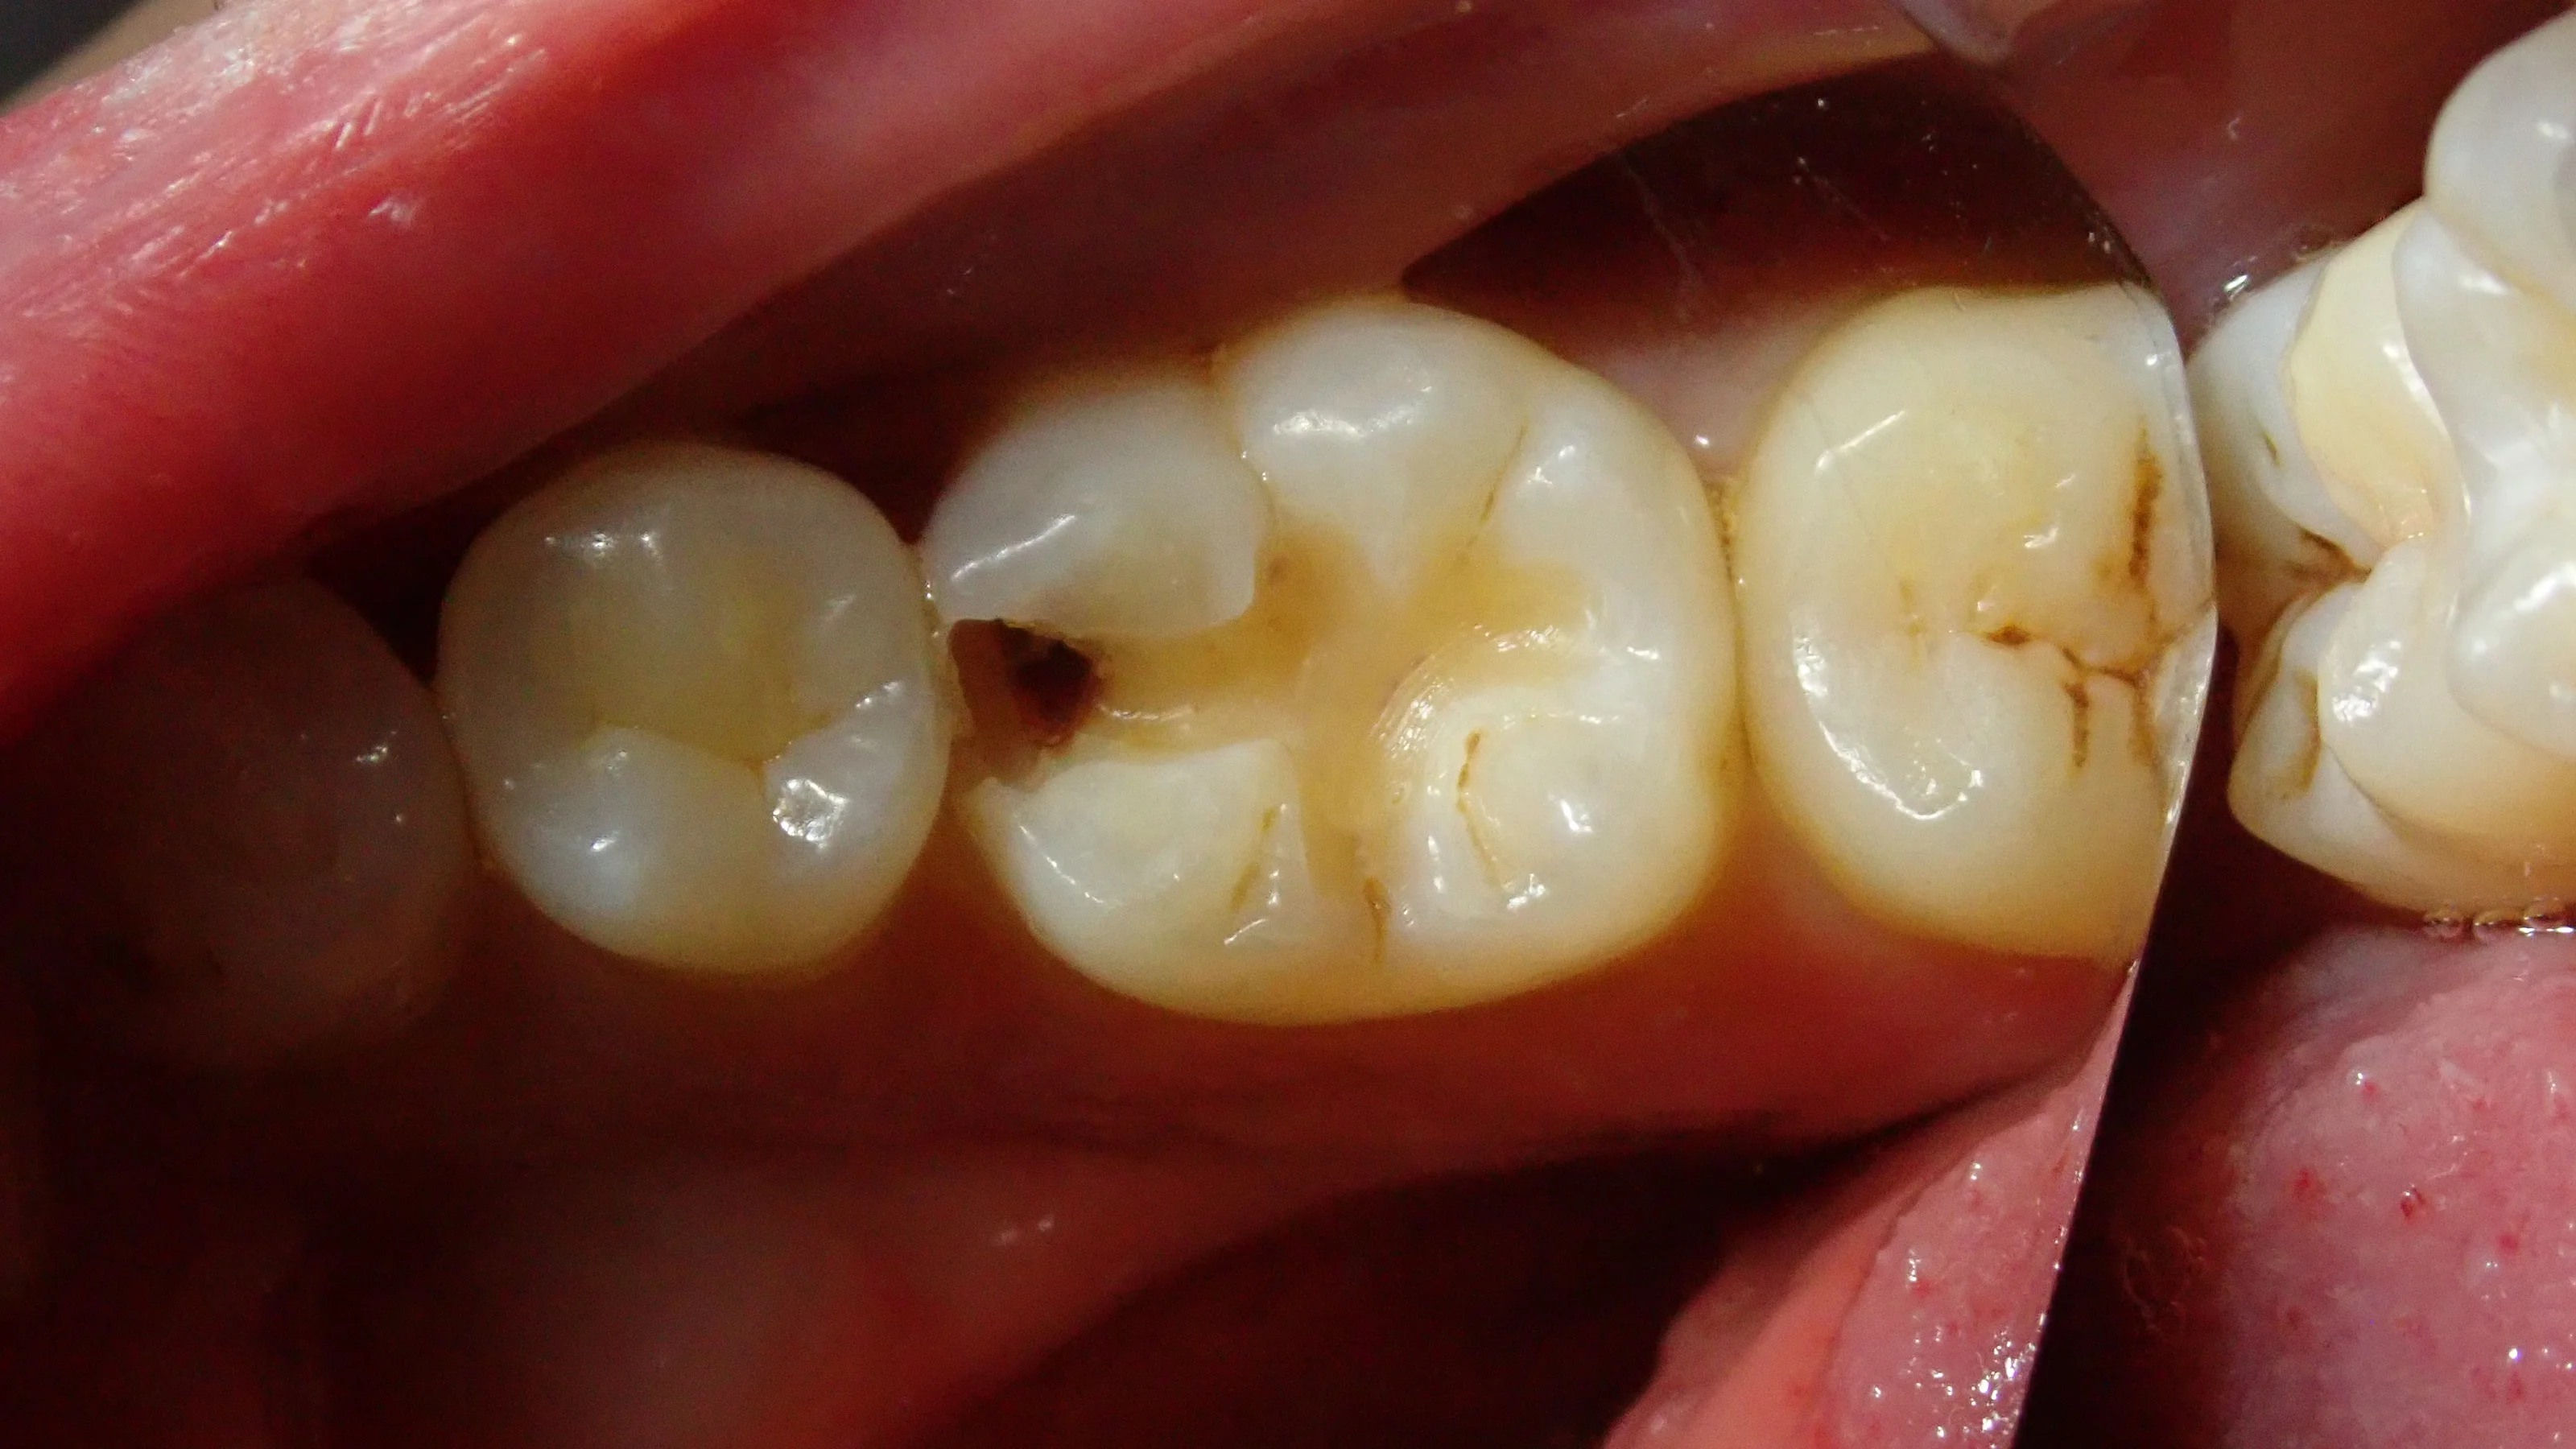

しっかりと麻酔を効かせた上で前に詰めていたCRを除去していくと・・・

レントゲン上で見るより結構大きく中に入り込んでいるようですね・・・

そして、虫歯を取り切った後の写真です。

一部着色が残っていますが、ここは特に虫歯とかではなく、ただ着色しているだけの部分となります。